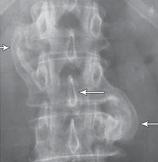

Рентгенограмма № 1. На снимке стрелкой указано расположение дугоотростчатых суставов позвоночника в состоянии нормы

Дугоотростчатые суставы осуществляют своеобразный контроль над движениями позвоночника. Например, они позволяют позвоночнику совершать движения, те же сгибание, разгибание, но в то же время ограничивают его движения в горизонтальной плоскости. Последнее позволяет при ротационных движениях позвоночника (от лат. rotatio — «кругообразное движение, вращение»), например при повороте туловища, при наклоне с поворотом, сохранять стабильное сочленение позвоночника и не проворачиваться позвонкам вокруг своей оси.